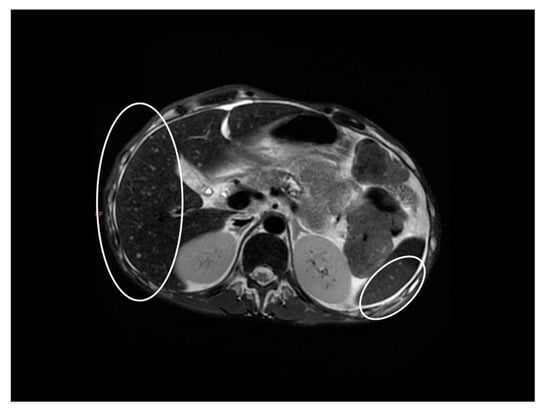

Chronic Calcifying Pancreatitis Associated with Secondary Diabetes Mellitus and Hepatosplenic Abscesses in a Young Male Patient: A Case Report

2. Case Report